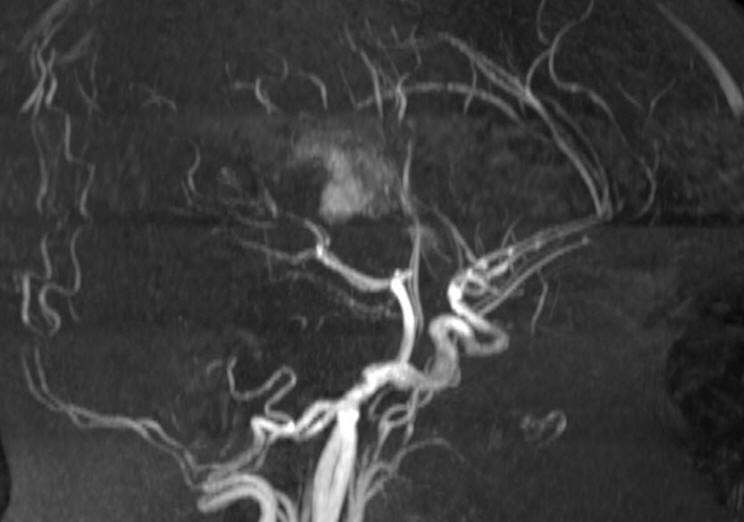

Fig-7: The hematoma in the bed of resected tumor. Notice that there is no arterial spasm.

The patient had smooth postoperative recovery, but later progressed transitory mutis after tapering Decadron, which resolved over 2 weeks. The challenge in this case was to preserve all the running veins in this area.